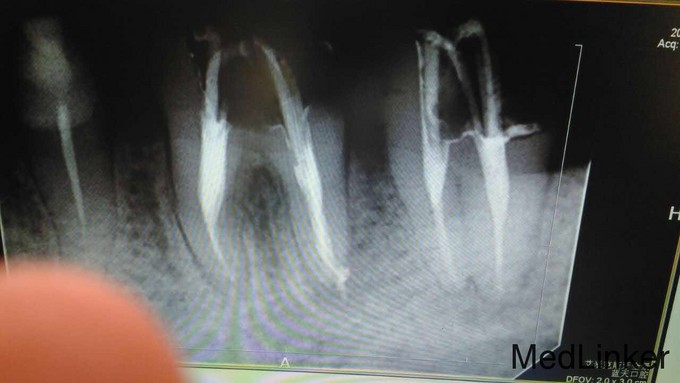

主诉:左上后牙疼痛一周余。 病史:左上后牙牙冠缺损一年余未治疗现疼痛明显夜间痛加重故前来就诊

1108根管治疗麟6

1108根管治疗麟9

1108根管治疗麟11